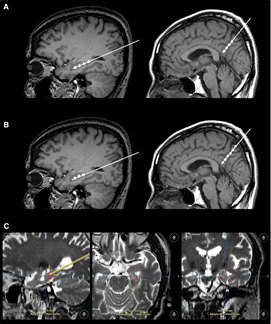

不仅如此,干细胞输注治疗安全可行。一项“立体定向脑内注射人间充质干细胞治疗AD病人”的临床试验结果表明,在治疗结束后的24个月随访时间内,患者没有出现与干细胞治疗相关的严重的不良反应[3]。

图2 立体定向注射(图片源于[3])